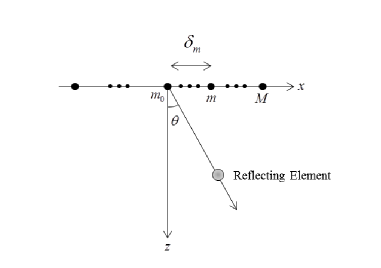

Consider an array comprised of transceiver elements aligned along the axis, as illustrated in Fig. 1. The reference element is set at the origin and the distance to the th element is denoted by . The image cycle begins at , when the array transmits an energy pulse in the direction . The pulse propagates trough the tissue at speed , and at time its coordinates are . A potential point reflector located at this position scatters the energy, such that the echo is detected by all array elements at a time depending on their locations. Denote by the signal detected by the th element and by the time of detection. It is readily seen that:

| (1) |

where is the distance traveled by the reflection. Beamforming involves averaging the signals detected by multiple receivers while compensating the differences in detection time. In that way we obtain a signal containing the intensity of the energy reflected from each point along the central transmission axis .

Using (1), the detection time at is since . Applying an appropriate delay to , such that the resulting signal satisfies , we can align the reflection detected by the -th receiver with the one detected at . Denoting and using (1), the following aligned signal is obtained:

| (2) | ||||

The beamformed signal may now be derived by averaging the aligned signals:

| (3) |

Such a beam is optimally focused at each depth and hence exhibits improved angular localization and enhanced SNR.